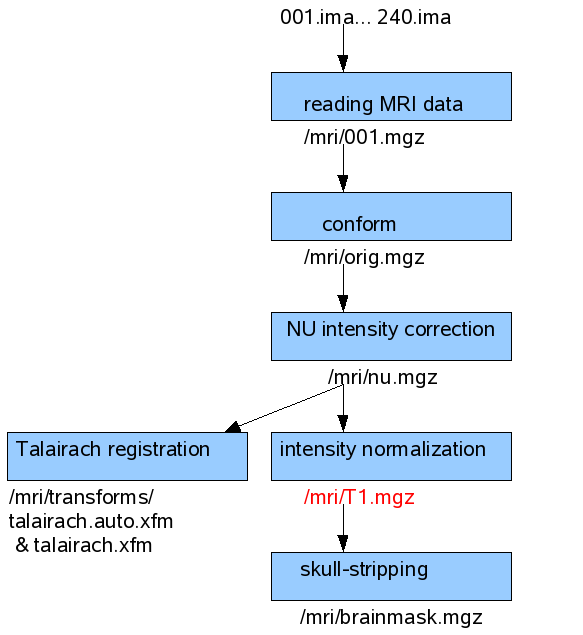

This figure shows the processing steps done by -autorecon1 when there is only one scanning run of one subject is available. The input and output file names are shown also for each step.

This first processing step takes around 1,5 hour.

First, it is averaging the multiple scanning runs together if they exist (output: $SUBJECTS_DIR/<subject’s name>/mri/rawavg.mgz), corrects small motions between them and conforms the data to 256 voxels (1mm size) for all directions (output: $SUBJECTS_DIR/<subject’s name>/mri/orig.mgz).

Then, a non-parametric non-uniform intensity normalization (N3) corrects for intensity non-uniformities (output: $SUBJECTS_DIR/<subject’s name>/mri/nu.mgz). Next, talairach transformation is computed (from nu.mgz) using MNI305 atlas, and outputs the transformation into $SUBJECTS_DIR/<subject’s name>/mri/transforms/talairach.auto.xfm and talairach.xfm.

Then, it performs an intensity normalization (intensity of all voxels are scaled) and gives the output $SUBJECTS_DIR/<subject’s name>/mri/T1.mgz. This is the volume that is used by the interactive analysis tool of MNE, mne_analyze where the MRI Viewer is using the T1.mgz volume together with the FreeSurfer tkmedit user interface. The tkmedit shows the MRI volume index and the Talairach coordinates. T1.mgz is also used as input for MNE for creating BEM meshes.

Last, the mri_watershed program is running that finds the boundary between the brain and the skull (output: $SUBJECTS_DIR/<subject’s name>/mri/brainmask.auto.mgz and $SUBJECTS_DIR/<subject’s name>/mri/brainmask.mgz).